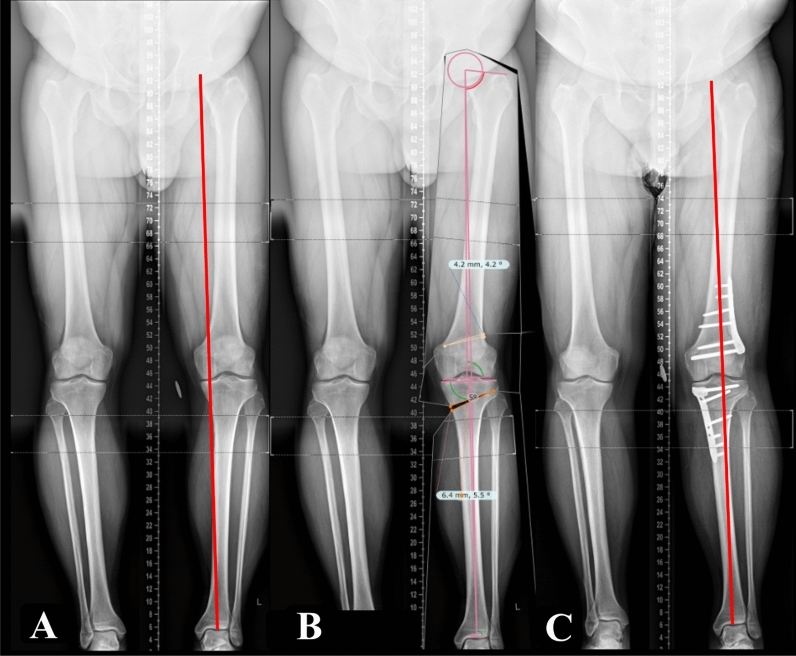

Results: A total of 58 valgization DLO cases were followed up to a mean of 10.8 ± 3 years. This comprised 74.1% males and 25.9% females, with a mean age of 47.9 ± 9.8 years and a mean body mass index (BMI) of 31.5 ± 6.3 kg/m2. The mean planned correction angles for HTO and DFO were 7.7° ± 2.7° and 7.7° ± 3°, respectively. Postoperatively, the mean mechanical tibiofemoral angle improved from -12.7° ± 3.9° (varus) to -0.4° ± 3.4° (i.e., centered around mechanical neutral), the mean medial proximal tibial angle improved from preoperative 84.3 ± 3.2° to postoperative 90° ± 2.5°, the mean mechanical lateral distal femoral angle improved from preoperative 91.6° ± 3.4° to postoperative 86.7° ± 2.5°, and the mean Mikulicz point improved from -5 ± 13.4% to 47.7 ± 14.7% (all p-values < 0.001). All PROMs significantly improved at 24 months follow-up (all p values < 0.001). The rate of osteotomy revision was 3.4%. The overall rate of total knee arthroplasty conversion was 5.2% at an average of 5.9 ± 3.1 years postoperatively. The complication rate was 8.6%. The 8- and 10-year survivorship was 97.1%, and 94.4%, respectively.

Conclusions: In this single-center series evaluating patients with varus knees and bifocal deformities, valgization double-level knee osteotomy (DLO) demonstrated favorable clinical outcomes, accompanied by a low complication rate of 8.6% and a 10-year survivorship of 94.4%. Radiographic findings from available imaging data were positive, although long-term imaging was not consistently obtained. Level of evidence IV retrospective cohort study.